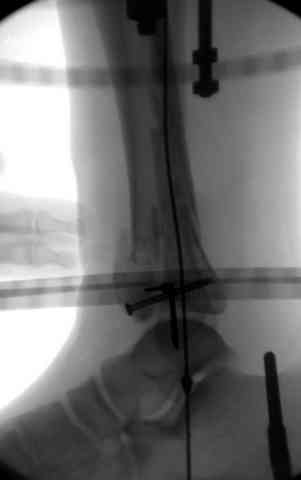

В первые часы после поступления больным экстренно накладывается простой фиксатор из двух поперечно проведенных стержней или сооружается "Delta

Frame" в зависимости от места локализации, и проводится дистракция.

Преимуществ у временного фиксатора много, во первых больной независим, если по другим показаниям нет необходимости находиться в стационаре, то больной может быть выписан домой с возможностью в амбулаторных условиях оценивать состояния мягких ткани на готовность к операции.

Наружным фиксатором обеспечивается длина конечности, предупреждается вторичное сокращение мягких ткани, что является немаловажным фактором для заживления послеоперационных ран. Без фиксатора сокращенные мягкие ткани легко травмируется во время манипуляций, трудно будет провести репозицию, ухудшается местное кровообращение и сохраняется посттравматический отек.

Здесь выставлена пара случаев перелома пилона, оба

случая леченные этапным наружным фиксатором.